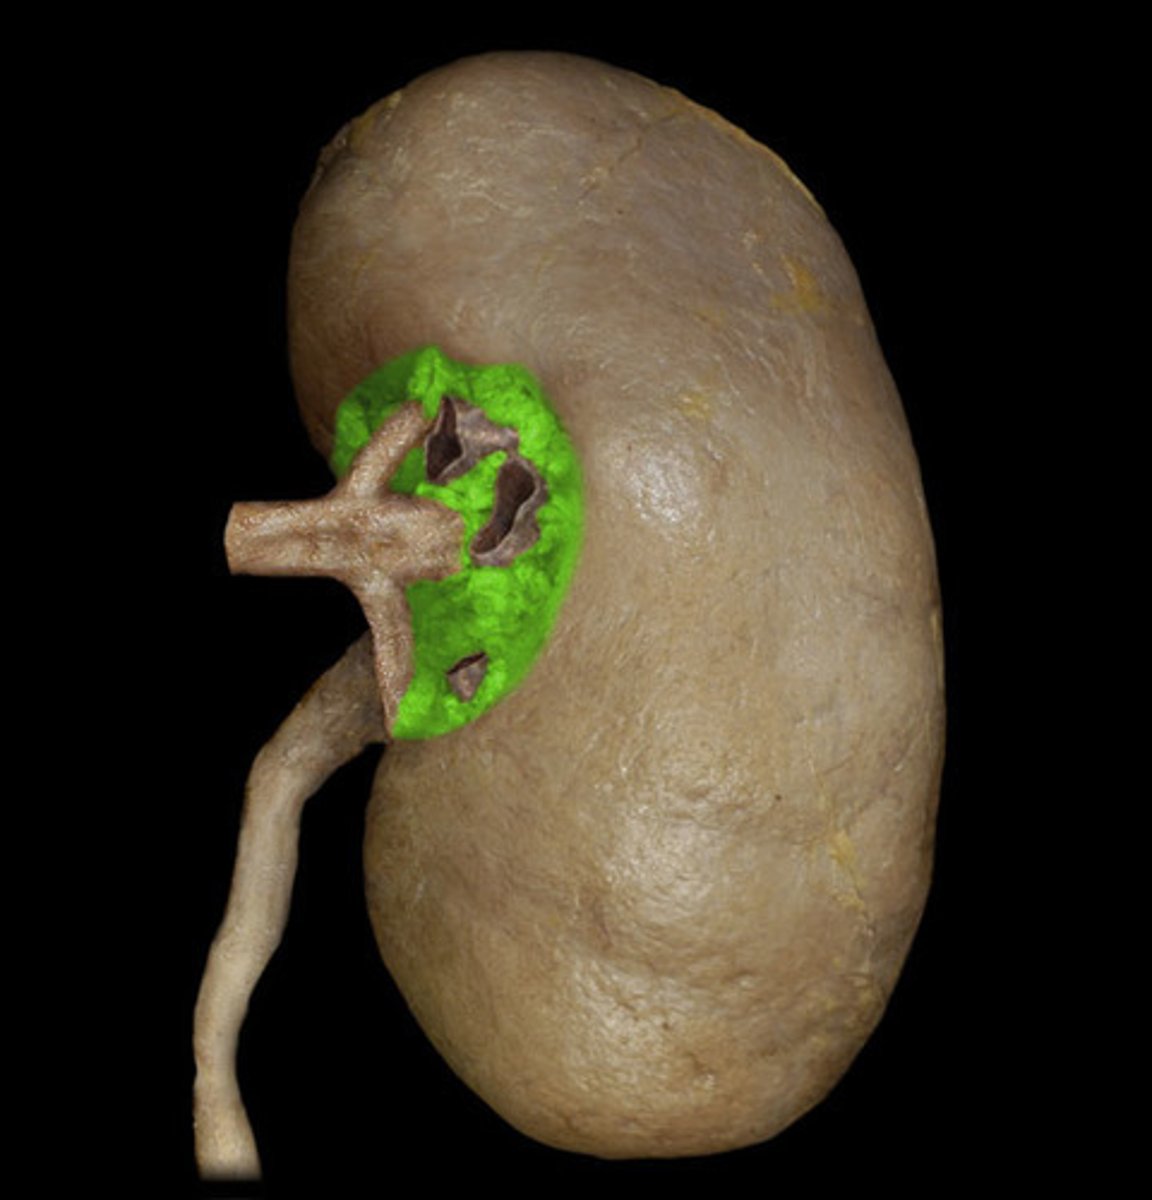

Renal Capsule

Renal Pelvis

Renal Hilum

Right Ureter

Left Ureter